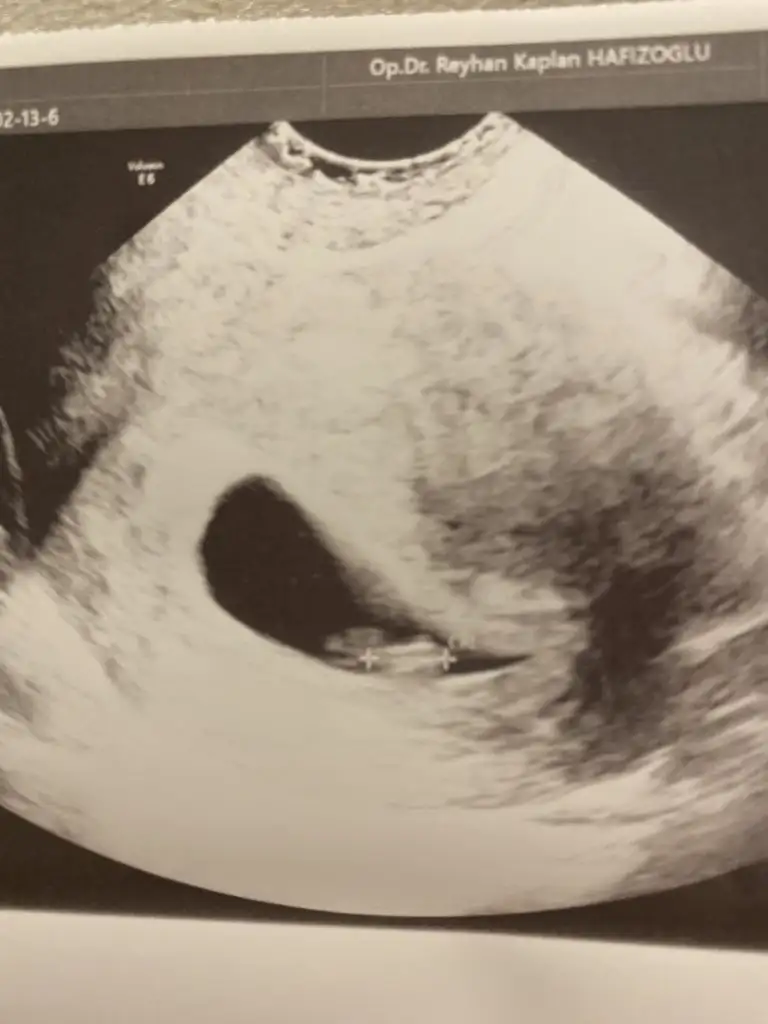

Merhaba inşallah bende Ekim annesi olacağım Yaş 27 Bursa Sat 11 ocak bugün keseyi gördük doktor 4 haftalık dediSevgili anneler listemiz oluşturulmuştur hayırlı olsunbeni etiketleyerek bilgilerinizi eksiksiz belirtirseniz sevinirim

Canım merhaba vajinal mi yoksa karından mi ultrasonun ona göre değişiyor cinsiyetKızlar iyi geceler. Bu gün kalp atışını duyduk öok şükür. Kese şeklinden cinsiyet tahmin edenler vardı banada bakabilir misiniz